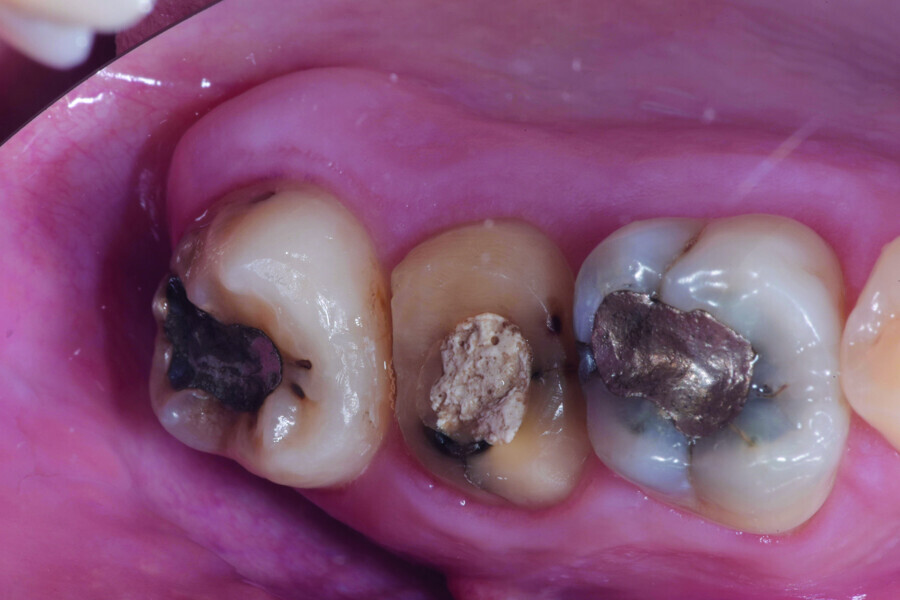

Fig. 12: Pulp chamber floor perforation, immediately after extraction.